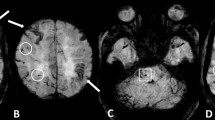

Of the 215 patients, 41 had single lobar or strictly deep CMBs and 89 had no CMBs, so 85 patients with multiple (≥ 2) lobar CMBs were included in the final analysis. Those who were excluded were not significantly different from those included in the analysis except for the average MMSE score and the prevalence of hypertension (Table 1). Among the 85 patients with multiple (≥ 2) lobar CMBs, 41 (48.2%) patients showed probable-CAA and the remaining 44 (51.8%) patients showed mix-CMBs. The clinical characteristics of the 85 patients are shown in Table 2. CMIs were detected in 9 of the 41 (22.0%) patients in the probable-CAA group, and 12 of the 44 (27.3%) patients in the mix-CMB group (p = 0.57). A flowchart of the patient selection is shown in Fig. 1. Representative images of CMIs from one patient each in the probable-CAA and mix-CMB groups are shown in Fig. 2.

Representative images of “Probable-CAA with CMIs” and “Mix-CMBs with CMIs”. Image from a patient with probable-CAA with CMIs: 3D DIR (a) and 3D FLAIR (b) images show cortical microinfarct (CMI) in the right parietal lobe (insert, white arrow). Susceptibility-weighted imaging (SWI) (c) shows cortical superficial siderosis (cSS; white arrow) and lobar cerebral microbleeds (CMBs; white arrowhead) in the right parietal lobe. Image from a patient with mix-CMBs with CMIs: 3D DIR (d) and 3D FLAIR (e) images show CMIs in the right parietal lobe (insert, white arrows). SWI (f) shows both deep and lobar CMBs (white arrowheads)